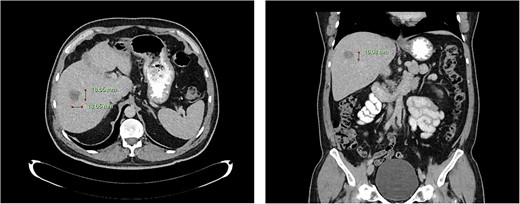

Computed tomography dated 15 January 2013 of the abdomen and pelvis measuring 10.50 mm (anterior–posterior) lesion at liver segment 5/6 in axial (left) and coronal (right) view.